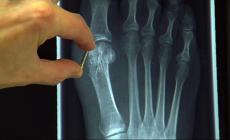

برغي لعلاج الكسور بدون الحاجة لإزالته!